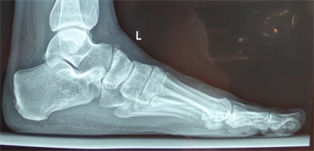

Figure 12. (a) Patient Nr. 3. Hallux valgus, pathologic DMAA; (b) Patient Nr. 3 Elevation of the Ist metatarsal of 3 mm.

Figure 13. Patient Nr. 3 Correction of the IM angle by lateralization, of the DMAA by derotation (lateral opening wedge), the head was also plantarized and a pronation malrotation was corrected. There is only a minimal contact between the osteotomy partners. A FDL Transfer was performed on the 2nd toe. Fixation with an interference screw. Immediate full weight bearing.

Figure 14. Patient Nr. 3 10 years result with complete correction of DMAA and all other components. No shortening of the Ist metatarsal.

Figure 15. Patient Nr. 3. The elevation of the I metatarsal was equalized by plantarization of the head of 3 mm.